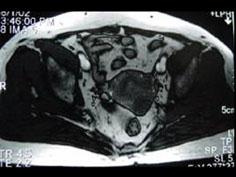

问题 55岁女性患者,绝经后阴道排液半年余,行MRI检查,如图所示,最佳答案是 ( )

选项 A、子宫肌瘤 B、子宫内膜癌 C、子宫颈癌 D、正常子宫 E、子宫内膜异位症

答案 B